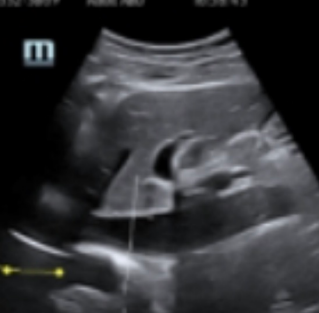

Trauma

Ultrasound is often used to detect intraperitoneal hemorrhage, pericardial tamponade, and hemothorax/pneumothorax ŌĆō using an?extended focused assessment with sonography for trauma?or FAST. While POCUS of the abdomen may not allow isolating the source of the bleed, it can be helpful to determine if a bleed has occurred, which gets them into the operating room faster in many cases.